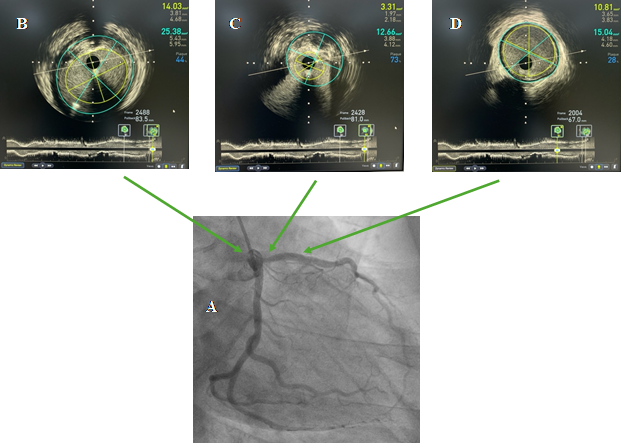

Trước can thiệp: A: hẹp 70% lỗ vào động mạch liên thất trước; B: tham chiếu đầu gần, đường kính mạch máu trung bình 4.5mm; C: vị trí hẹp nhất, diện tích lòng mạch 3.31 mm2, gánh nặng xơ vữa 73%; D: tham chiếu đầu xa, đường kính mạch máu trung bình 4.0mm